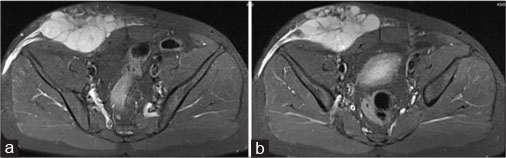

A 40-year old male patient presented with swelling over the anterior abdominal wall on the right side in lower abdomen for 1 month which was rapidly increasing in size. There was a history of weight loss. The mass was painless. The ultrasonography showed a large, well-defined solid mass with lobulated outlines in anterior abdominal wall in the right paraumbilical and hypogastric region [Figure 1]. The mass was seen in the subcutaneous plane, causing extrinsic compression on adjoining right rectus abdominis and external oblique muscle. It was predominantly hypoechoic with small areas of the necrosis in its center and showed mild vascularity on color Doppler. No calcification was seen. Plain and contrast enhanced computed tomography (CT)-scan of the abdomen and pelvis was performed. A large, well defined solid mass with lobulated outline measuring approximately 96 mm × 38 mm × 98 mm in transverse, anteroposterior and craniocaudal dimension was noted in the anterior abdominal wall on the right side in right iliac region extending to hypogastric region. It was slightly hypodense with respect to muscle on the plain study with a CT value of 35–45 HU and showed a mild heterogeneous enhancement in contrast study (CT value 55–65 HU). No calcification was noted. The mass was in subcutaneous plane and was extending anteriorly up the skin. Posteriorly, it was causing mass effect on the right rectus abdominus and adjoining external oblique and internal oblique muscles which were compressed and displaced posteriorly with obliteration of intervening fat planes [Figure 2]. An enhancing vessel was noted in the right rectus abdominus extending into the mass suggestive of neovascularity. No intra-abdominal extension was noted. Rest of the abdominal wall appeared normal. No hepatic or adrenal metastases, intra-abdominal lymphadenopathy noted. On magnetic resonance imaging (MRI), the mass appeared slightly hyperintense with respect to muscle on T1-weighted image, heterogeneously hyperintense on T2-weighted image (T2WI), and hyperintense on short tau inversion recovery and showed restricted diffusion on diffusion-weighted imaging with low apparent diffusion coefficient (ADC) values (ADC = 800). It was causing mass effect on the right rectus abdominus and adjoining external oblique and internal oblique muscles [Figure 3] [4] [5] [6].

| Figure 1: Ultrasound of the anterior abdominal wall with linear probe showing well-defned solid hypoechoic mass with lobulated outlines in the right iliac fossa in subcutaneous plane (a) causing extrinsic compression and posterior displacement of abdominal wall muscles (b)